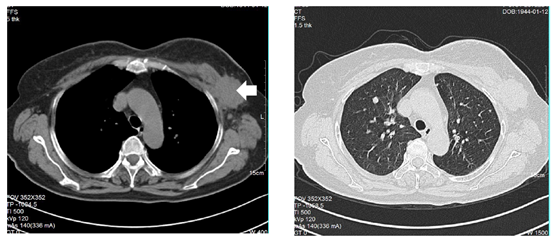

胸部CT:两肺多发类结节,考虑转移瘤。附见:左乳肿块;左锁骨上、双侧腋下淋巴结肿大,考虑恶性肿瘤,请结合专项检查。

图片1.png

基线胸部CT

图片2.png图片3.png

治疗前后,胸部CT

这是一例绝经后的高龄老年女性,初诊为cT4N3cM1 IV期,Luminal A型伴多发肺转移的患者。一线治疗给予靶向CDK4/6抑制剂哌柏西利联合来曲唑。治疗4个月后,患者溃疡面愈合,皮肤色泽恢复,肺部病灶缩小,总体疗效评估为PR,目前患者PFS已经超过19个月,仍在持续获益中。治疗过程中仅出现了2级血液学毒性,总体耐受良好。

结合本例患者,患者初诊即伴有多发肺转移,但未出现淋巴管炎伴呼吸困难等内脏危象症状,因此一线治疗首选靶向治疗CDK4/6抑制剂联合内分泌治疗,治疗后患者肺部病灶逐渐缩小,最终达到PR状态。